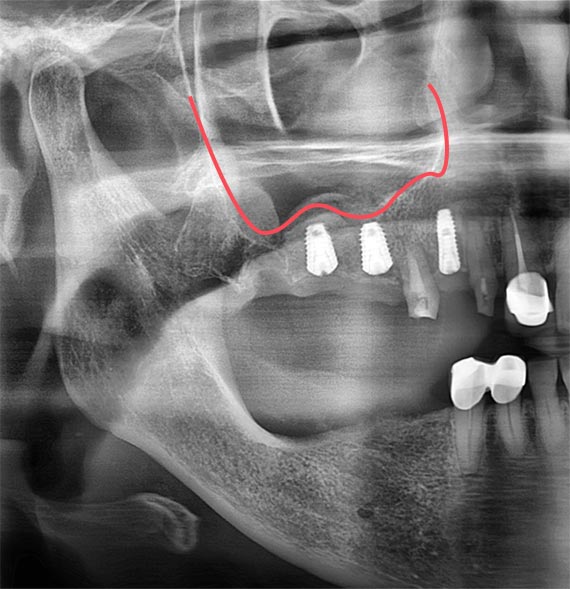

상악의 어금니를 뽑고 오랜 시간이 지난 경우